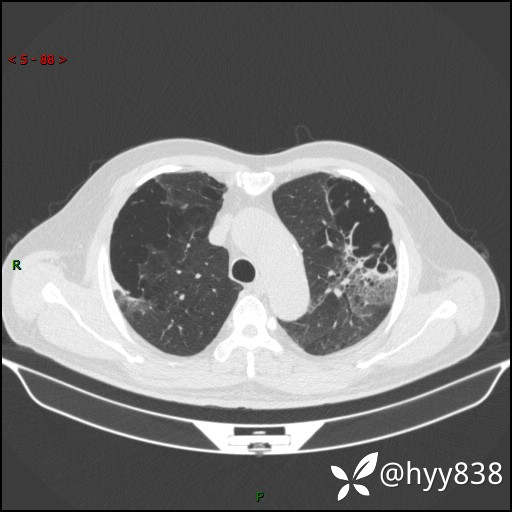

一周后胸部CT